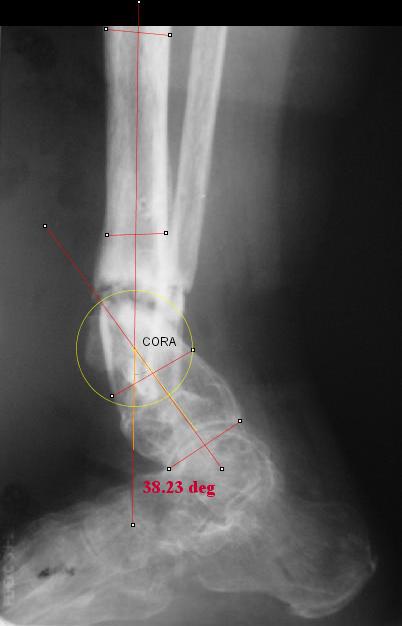

I played with your image using some orthopedic software we have been developing for digital

image analysis.

What you see marked up is the intercept of two mid-line tool centre lines, used to define the CORA. An angle tool gives the angular deformity and a circle tool is applied to show that a correction around the CORA through the old # will restore alignment without much translation.